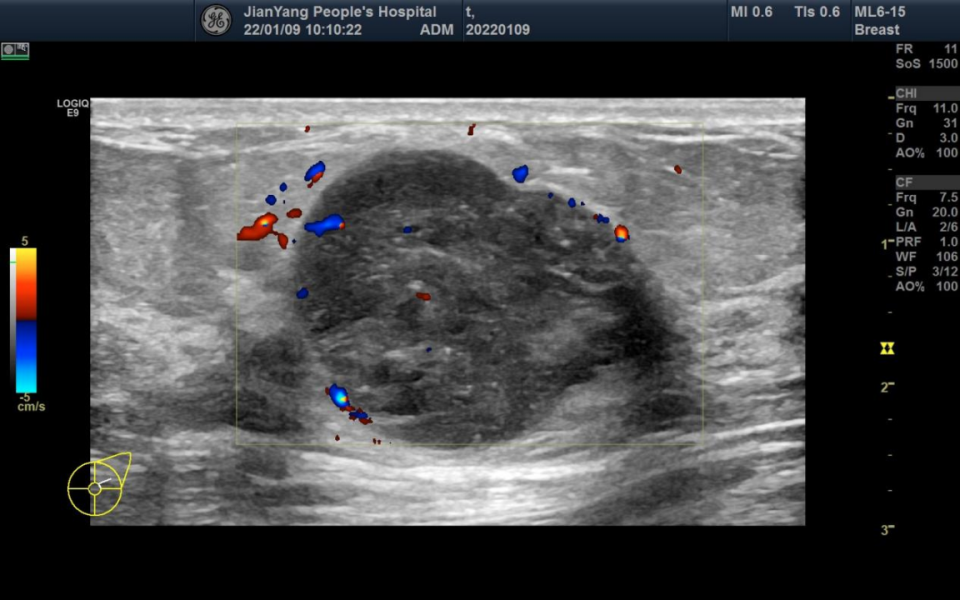

申请超声检查图像如下:

图片图 1 左乳 2 点钟方向肿物

两侧乳房切面形态轮廓正常,层次清楚,腺体回声不均匀,左乳 2 点钟方向距乳头约 20 mm 处可见范围约 28.3 mm x 22.4 mm x 28.1 mm 的低回声团,略呈分叶状,边界清楚,内可见不规则无回声区,其内可见较多条状血流信号。

双乳导管未见明显扩张征像。CDFI:余腺体内未见异常血流信号。

超声提示:左乳低回声团 BI-RADS 4A 类

MBC 多见于绝经后妇女,肿块较大,超声特征多表现为不均匀低回声,边缘光整,形态不规则,平行于皮肤,无钙化或微小钙化,后方回声无改变或增强,伴或不伴腋窝淋巴结转移,Adler 分级 Ⅱ~Ⅲ 级多见,阻力指数多>0.7。与间叶化生癌相比,鳞状细胞癌多表现为直径较大、呈囊实性回声、腋窝淋巴结无转移。